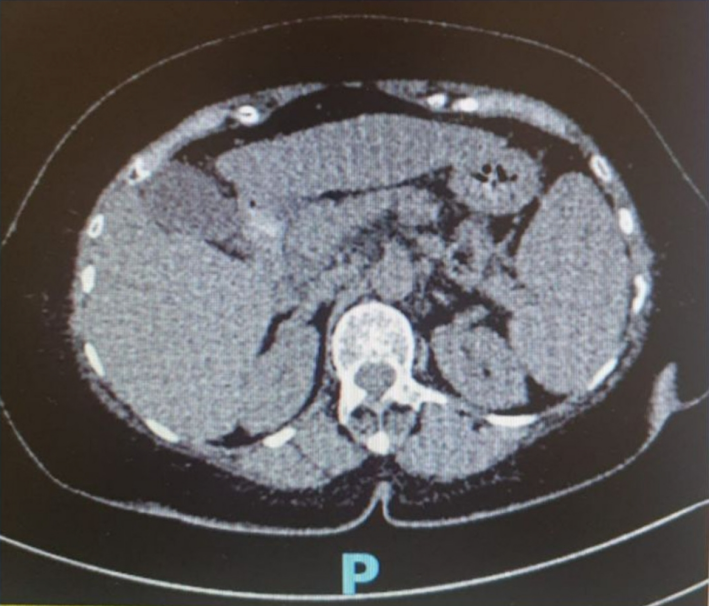

图2 腹部CT

MAFLD患者可早期出现 CSPH,其病理生理机制为肝脏脂质蓄积、肝细胞气球样变、肝细胞损伤及肝血窦内皮功能障碍共同导致肝微血管收缩,肝内血管阻力增加,肝血流量减少。上述病理生理改变提示,CSPH可发生于进展期肝纤维化或肝硬化之前。此外,本病例患者合并2型糖尿病,胰岛素抵抗作为肝外危险因素,进一步损害肝微循环,促进早期门静脉高压的发生。本例患者腹部CT未见明确肝硬化改变,但已出现脾大、食管静脉曲张、血小板减少等门静脉高压表现。该差异可能反映了CT成像在检测微小纤维化或早期肝窦病变方面的局限性。提示对于老年肥胖MAFLD患者,需结合无创评估、内镜检查及临床判断的综合诊断策略。